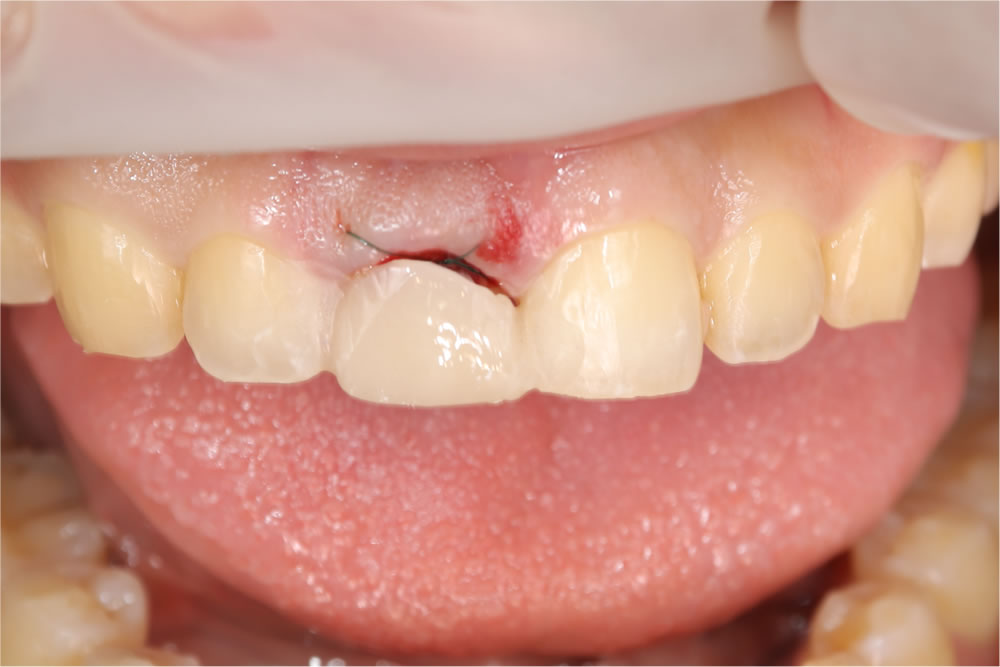

当該歯を部分的に抜歯(ソケットシールドテクニック)

ソケットシールドテクニックを用いて当該歯を部分的に抜歯しました。

次に行ったのが、前歯のインプラント治療です。この症例では、「ソケットシールドテクニック」という方法を選択しました。

これは、抜歯する歯の唇側の歯根をあえて残すことで、【歯ぐきの下がり】【骨の吸収】を最小限に抑えるテクニックです。

インプラント埋入後はすぐに仮歯を装着し、「歯がない期間」を作らないよう配慮しました。